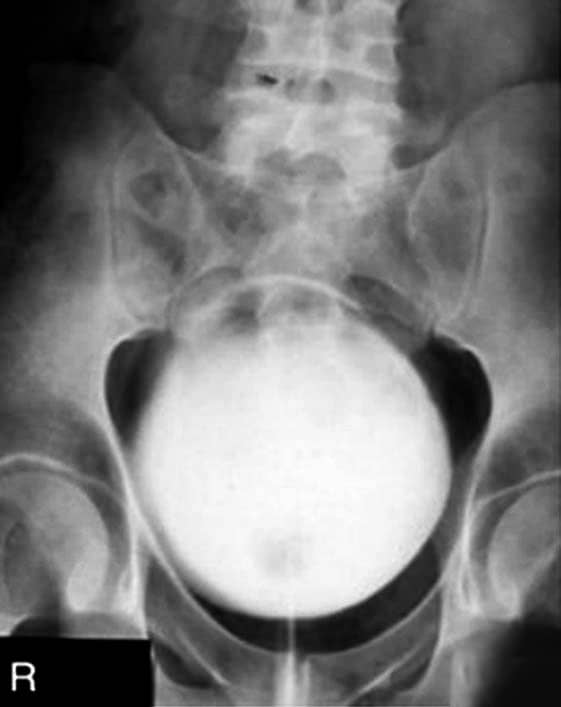

Incidência AP – Urografia excretora – Pós-miccional

Urografia excretora pós-miccional.

Justificativa para realização do exame

Visualizar aumento da próstata e o prolapso da bexiga; na posição de pé (ortostática) mostra a nefroptose (mudança posicional dos rins).

Principais estruturas demonstradas

Todo o sistema urinário, com contraste residual.

Fatores técnicos e posicionamento

• DFF: 1m.

• Tamanho do filme/receptor de imagem e sentido: 35x43cm no sentido longitudinal.

• Técnica de referência: 22mAs e 75KV, na mesa (desejável fazer um PA) ou em ortostática.

• RC: perpendicular no centro do filme e ao nível das cristas ilíacas.

• Posição do paciente e da parte ou região do corpo: paciente em decúbito dorsal, com os braços ao lado do corpo, fornecendo um travesseiro e um suporte sob os joelhos para diminuir a tensão lombar.

• Respiração: parar a respiração e expor durante e expiração lenta.

Atenção

Essa incidência radiológica é feita de pé, com alternativas em decúbitos, principalmente o ventral com a incidência em PA. O paciente tem que estar próximo a um banheiro, de preferência dentro da sala de exames, para urinar, a comando do médico condutor do procedimento para a efetividade do exame de imagem.